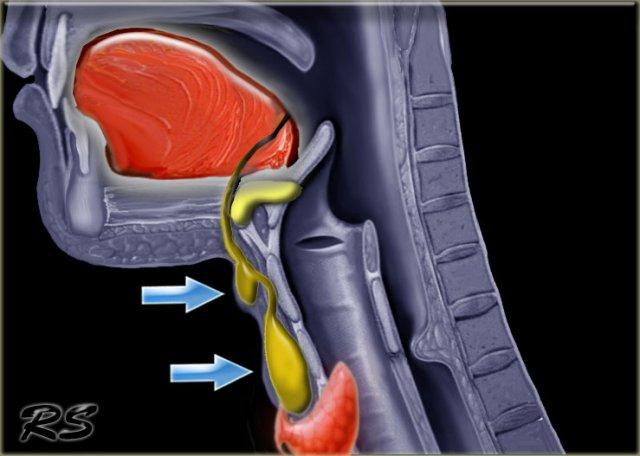

Ống giáp lưỡi chạy từ nền lưỡi tại lỗ manh tràng đến tuyến giáp.

Tuyến giáp phôi thai di chuyển qua ống để đến vị trí bình thường cuối cùng của nó.

Thông thường, ống giáp lưỡi sau đó sẽ thoái triển, nhưng khi ống tồn tại dai dẳng, nang ống giáp lưỡi có thể phát triển ở bất kỳ vị trí nào dọc theo đường này (hình).

Nang ống giáp lưỡi di chuyển lên trên khi thè lưỡi ra hoặc trong khi nuốt (xem video tiếp theo).